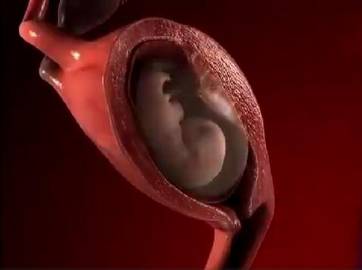

妈妈从孕育到孩子的出生,中间要经历10个月。网上有一组生动形象的动图,可以看出这十个月妈妈究竟经历了什么,这个期间,宝宝每个月在妈妈的肚子里的状态都是不一样的。如果有看过一个胎儿从开始孕育到出生10个月的不同形态,你就会感受到生命的神奇,宝宝在妈妈肚子里每个月不同的形态。

孕妈在刚刚怀孕的时候,宝宝那会儿还只是一个胚胎,被子宫包裹住也就只有鸡蛋那么大。如果孕妈反应激烈,呕吐恶心,这个时期的孕妈是非常难受的。

当宝宝在妈妈肚子里呆到第二个月的时候,胎儿从一个胚胎变成了雏形,而且孕妈的子宫壁也会越来越薄。